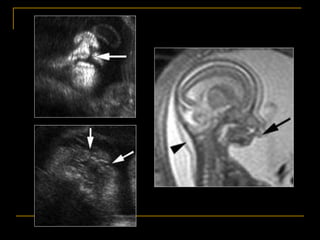

Embryology

AJR 2004; 183:229-235